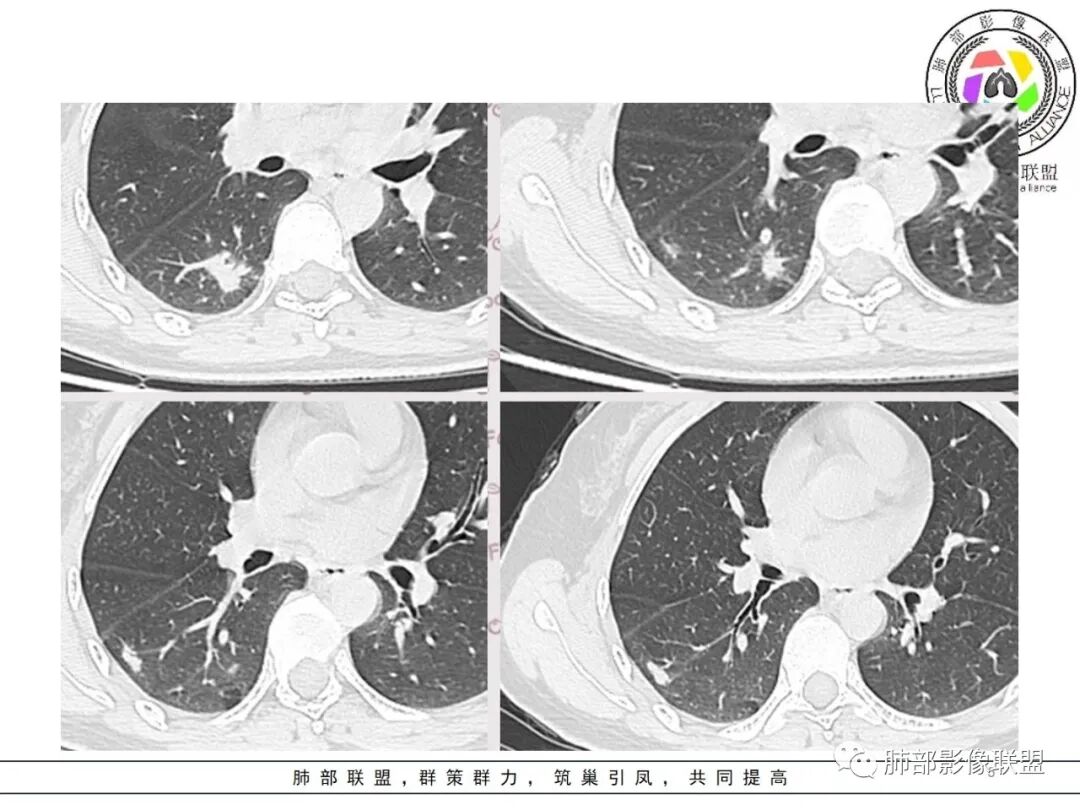

右肺下叶背段两个病灶

大的病灶:长轴边界清,偏平直,胸膜凹陷,周围长毛刺

支气管进入病灶内,远端稍扩张、圆钝

密度均匀

小的病灶更平直,支持炎性,隐球菌要考虑